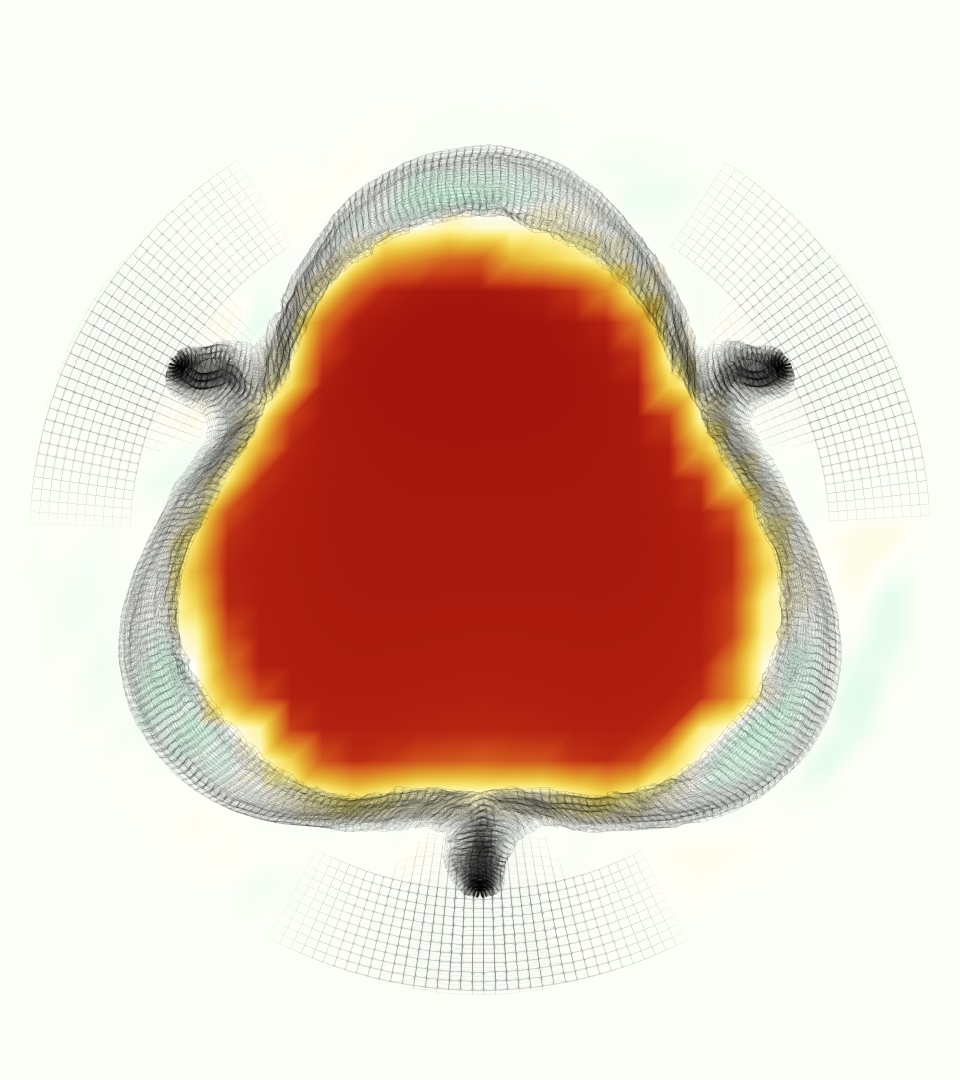

The gross morphology of the model valve that emerged from this process is shown in Figure 4. The free edge was 2.87 cm, corresponding to 3.3 cm in the predicted loaded configuration. After the pinching the leaflets together at the commissures, this left approximately 2.1 cm of free edge rest length per leaflet free to move independently of the other leaflets, within measurement error of ±0.1 cm from the free edge length of 2.2 cm measured on the prostheses. The leaflet rest height was 0.94 cm corresponding to a predicted loaded height of 1.44 cm. The measured leaflet height of 1.3 cm is nearly the predicted loaded height of 1.44 cm, which may be because the leaflets are so compliant in the radial direction, that pulling them flat to measure them achieved substantial stretches. The fiber orientation of the model runs from commissure to commissure and qualitatively matches experimental observations [38], though direct quantitative comparison is beyond the scope of this work. One minor limitation is that we do not add bending rigidity to the leaflets, beyond what emerges from the thickening process described above, and thus may not accurately capture leaflet flutter or other similar behaviors. Based on the thickness of mm, we estimated the mean tangent modulus at the predicted loaded stretches as dynes/cm2 circumferentially and dynes/cm2 radially. The prosthetic valve tissue is fixed in glutaraldehyde, and literature values for the fully-recruited circumferential tangent modulus of fixed porcine aortic valve tissue vary widely. Based on the experimental measurements of Billiar and Sacks and their constitutive law for valves fixed under 4 mmHg of pressure, we evaluated their constitutive law at the relevant stretches and and estimated the circumferential tangent modulus to be dynes/cm2 [6]. Rousseau et al. reported moduli ranging from to dynes/cm2, depending on the applied preload during fixation [36]. Sung et al. reported moduli ranging from to dynes/cm2, depending on fixation pressure [43]. Thus our estimated tangent modulus falls within the range of existing studies, so we considered our resultant modulus in good agreement given the complexity of the steps involved, phenomenological nature of the constitutive law and uncertainties in experiments. We do not have access to the precise material properties of the prosthetic valve, and further, the only literature we could find on the material properties of a similar prostheses reported the tangent modulus at one particular loading, which did not appear to be at a relevant stretch for comparisons with our model [19]. Thus, our model has material properties in a reasonable range for a fixed aortic valve prostheses (placed in the pulmonary position in our simulations), but it does not directly model the material properties of the prostheses.

At = 0, the axial slice directly at the valve annulus shown in columns 1 and 2 in Figure 6, there was excellent agreement between the simulation and experiment over the cardiac cycle in the speed and shape of the jet through the valve. In both cases, the axial velocity increased as the flow accelerated during systole and the valve leaflets opened, then decreased during diastole with slight negative velocity before the valve leaflets were fully closed. The forward flow through the valve annulus did not form a full circle, but rather developed a triangular shape with a point of the triangle forming along the interior curve of the vessel, at the bottom of the axial slices. At = 0, the points of this triangular jet shape aligned with the commissures of the valve. This shape persisted during peak systole and was well-matched by the simulation.

The axial slice = 0.625 cm, shown in columns 3 and 4 in Figure 6, cut through the support scaffolding of the valve and the leaflets when they are open. In the experimental data, the shape of the jet changed as it moved downstream. A triangular shape occurred, but the points were then aligned with the middle of each open leaflet as opposed to the commissures. Those points were also more rounded than they were at = 0. The peak velocity of the jet was faster at = 0.625 cm than at = 0, as the flow accelerated through the open valve leaflets. The simulation produced these features at = 0.625 cm. The triangular shape of the jet shifted similarly, and its speed increased compared to the upstream slice. As the flow decelerated into diastole, the jet shape remained roughly triangular but diminished in intensity before disappearing after valve closure.

The jet continued to develop at = 1.25 cm, an axial slice immediately downstream of the valve scaffolding and open leaflets, shown in columns 5 and 6 in Figure 6. In the experimental data, the points of the triangular jet shape extended further towards the vessel wall. In addition, regions of reversed flow developed in the locations downstream of the commissures, resulting in curved sides to the shape of the jet. Each tip of the jet was unique, due to variations in the individual leaflets in the physical bioprosthetic valve. These variations are apparent in the velocity fields, possibly because the jet edges are similar enough cycle to cycle that irregularities are still being captured even with phase averaging. Further discussion of these features can be found in Schiavone et al. [39], which showed that the jet tip shapes occurred in different pulmonary anatomies, demonstrating that they were likely due to inherent properties of each leaflet. The leaflets in the mathematical model of the valve are identical, so these nuances in leaflet variation could not be replicated. The simulation did capture some of the extension of the tips of the jet, as they were closer to vessel wall at slice = 1.25 cm than = 0.625 cm. The curves in the triangular sides of the jet were also present in the simulation, though they were less pronounced than the experimental data. At both = 0.625 cm and = 1.25 cm, the jet shape in the simulation was smoother than the jet in experiment. It is possible that the free edges of the leaflets in the mathematical model are not fully replicating the behavior of the physical leaflets of the bioprosthetic valve, in particular the amplitude or frequency of leaflet flutter, leading to the variations seen in the jet shape at = 1.25 cm downstream of the leaflet edges. The simulation, however, does capture the key features of the triangular shape and speed of the jet. Overall, qualitative comparisons demonstrated that the simulation reproduced key features of the flow during systole and diastole.